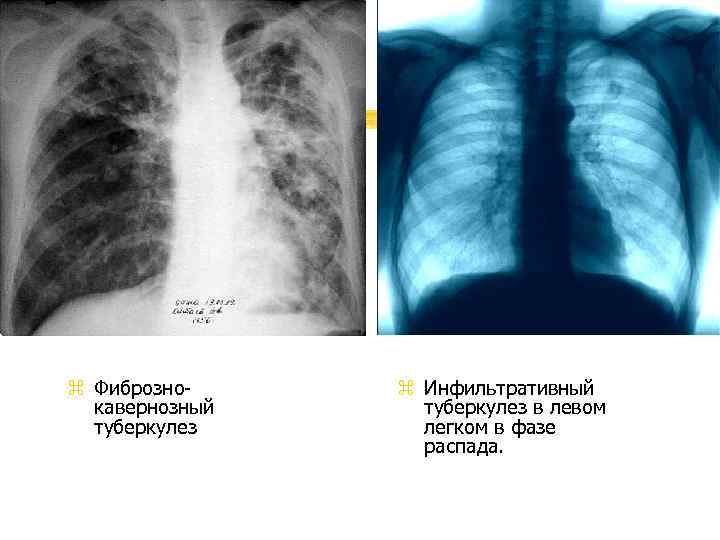

Иллюстрации по теме очагового и инфильтративного туберкулеза